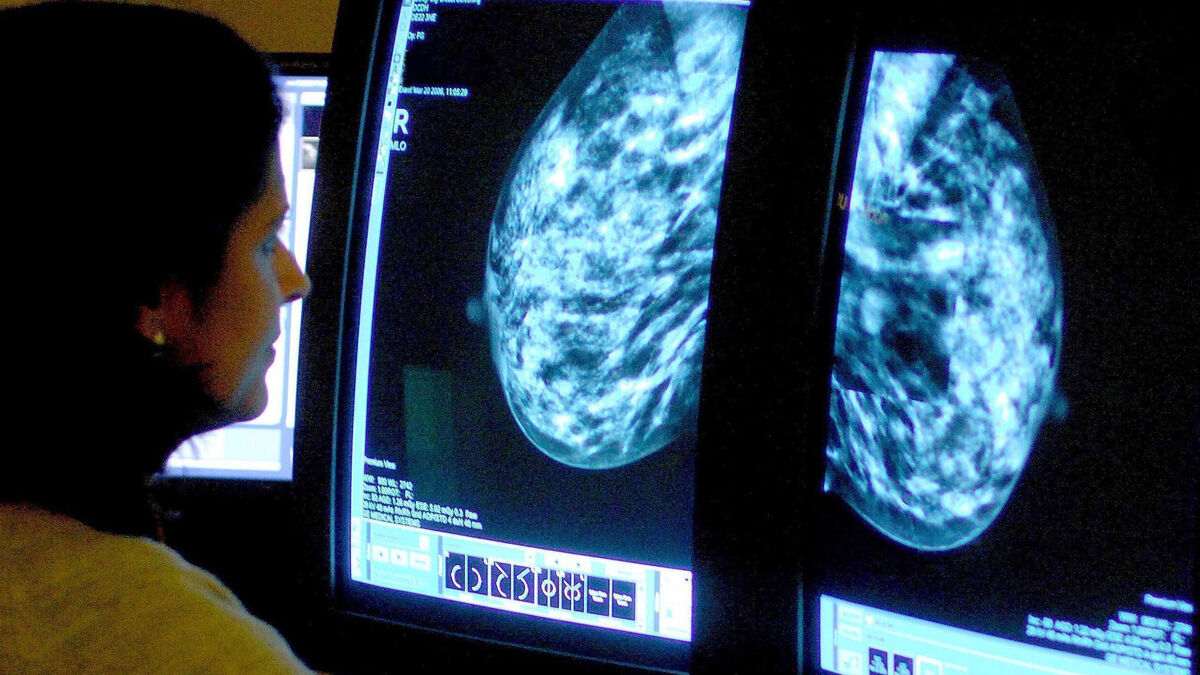

Signs of heart disease can be picked up in breast cancer screenings through the use of artificial intelligence (AI), researchers have found.

Experts used AI to look for calcification in breast arteries, a substance that increases the risk of heart attack, stroke and early death.

Adding AI to breast cancer screenings in this way could help find thousands of women with undiagnosed heart disease, according to the largest study of its kind.

AI was used to look for calcium deposits in the arteries of breast tissue, which is known to harden arteries and can increase the risk of heart attack and stroke.

Researchers noted whether the calcification was severe, moderate, mild or absent and compared this with data on whether women went on to suffer serious heart disease, including stroke, heart attack or early death.